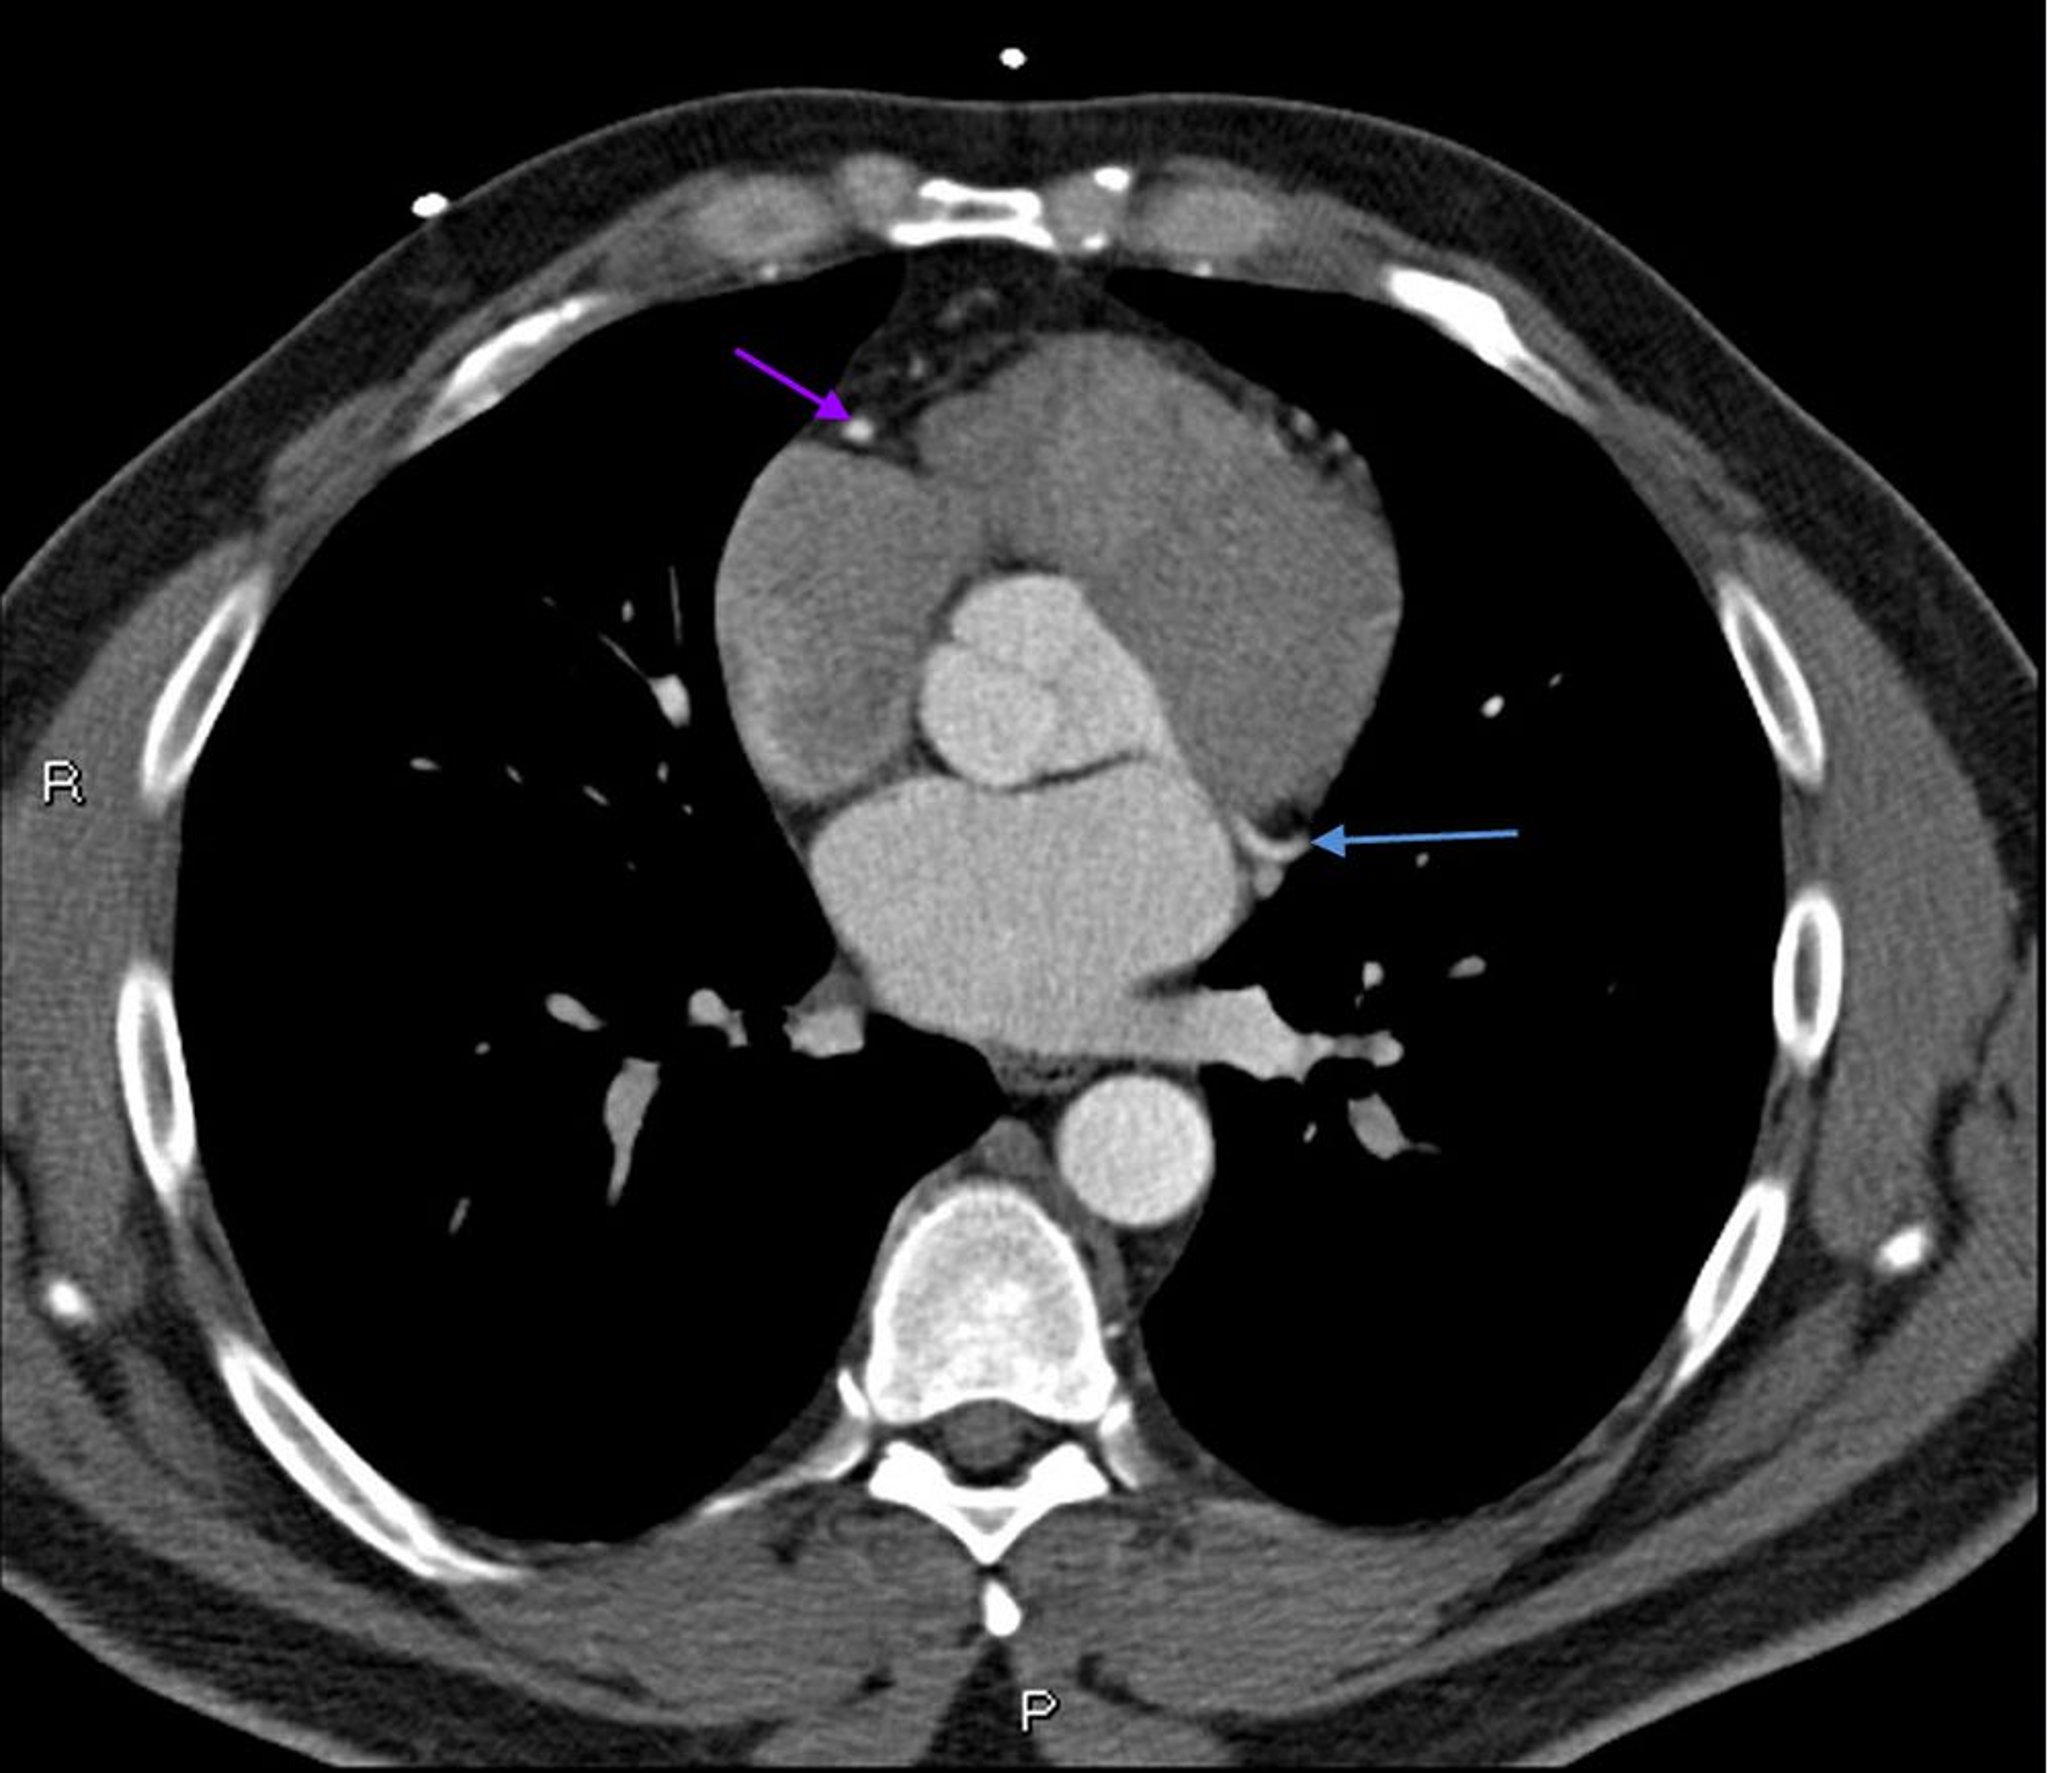

TC com contraste mostrando artérias coronárias normais – Diapositivo 6

Essa TC com contraste mostra artérias coronárias normais. A artéria esquerda principal é indicada pela seta vermelha. As artérias descendente anterior esquerda e circunflexa esquerda são indicadas pelas setas verde e azul, respectivamente, e a artéria coronária direita é indicada pela seta roxa.